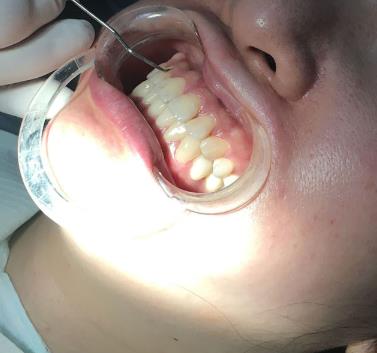

牙齒矯正案例展示:

因為我的牙齒不整齊的問題,小的時候經(jīng)常受到朋友的譏笑,導(dǎo)致我特別的自卑,那時候也想過去醫(yī)院做牙齒矯正手術(shù),但是由于我的家庭條件不是很好,拿不出那么多的錢去醫(yī)院做牙齒矯正手術(shù),所以這個想法就沒有。等我上了班以后,錢包里有了些積蓄,我要做的第一件事情,就是去醫(yī)院做牙齒矯正手術(shù)。有了想做牙齒矯正手術(shù)的想法,就開始在網(wǎng)上查詢當(dāng)?shù)氐目谇会t(yī)院,我想在當(dāng)?shù)刈鍪中g(shù),比較方便以后復(fù)診。四川省人民醫(yī)院口腔科

經(jīng)過慎重的對比后,我覺得四川省人民醫(yī)院口腔科較為正規(guī),口碑也不錯,就預(yù)約了手術(shù)時間,來四川省人民醫(yī)院口腔科做牙齒矯正手術(shù)了。面診了醫(yī)生以后,李崢醫(yī)生給我看了他做的許多成功的牙齒矯正案例,我也問了很多手術(shù)問題,李崢醫(yī)生都有耐心的一一解答,回答的很專業(yè),提出的建議也很中肯。

李崢醫(yī)生說像我牙齒的情況,不適合帶隱形牙套,給我推薦了一種3m自鎖托槽牙套,這種牙套戴在牙齒的里面,別人也不會發(fā)現(xiàn)做了牙齒矯正手術(shù)。瞬間覺得李崢醫(yī)生的醫(yī)德特別高尚,并不會因為賺錢而推薦價錢小貴的隱形牙套。

兩周以后,我就帶上了牙套。剛帶上牙套那會,我的很不舒服,牙套磨嘴不說,牙齒酸軟無力,我堅持了一周左右,牙齒就變得舒服多了。

這個牙套我?guī)Я艘荒臧氲臅r間,就成功的摘掉了,現(xiàn)在牙齒變得又整齊又潔白,整個人不但變漂亮了,而且變得更加有自信,無論做什么事情都充滿了熱情。我較為的開心。